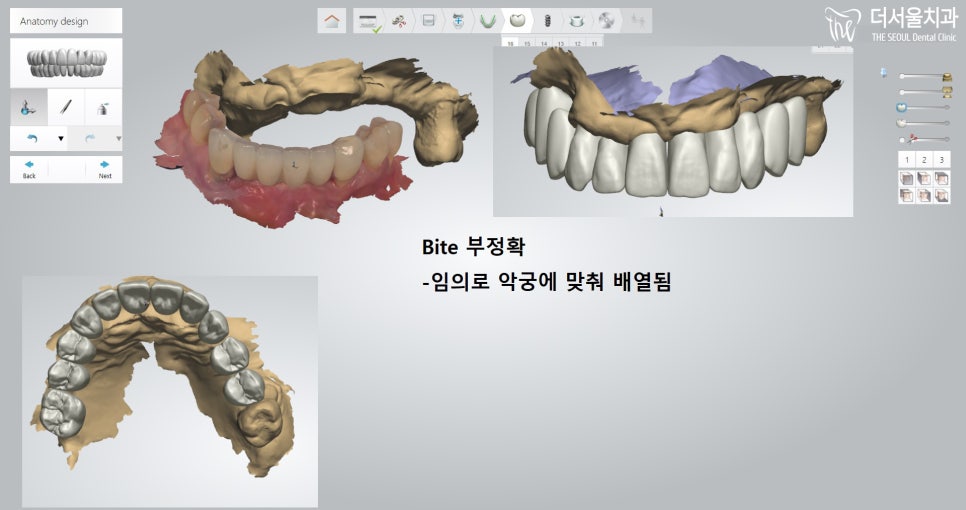

그리고 임플란트 식립이 되지 않는

구치부(어금니) 쪽은 부분 틀니를 이용하여

구강 활동을 하실 수 있게끔

보철 제작에 들어갔는데요.

아무래도 전체적으로

교합이 잘 맞아 떨어지는게 중요한데,

한꺼번에 다 맞추기가 정말 어렵습니다.

그래서 성남 치과의원은

여러 번 시도를 하고 나니,

환자분께 맞는 보철을 제작할 수 있었습니다.